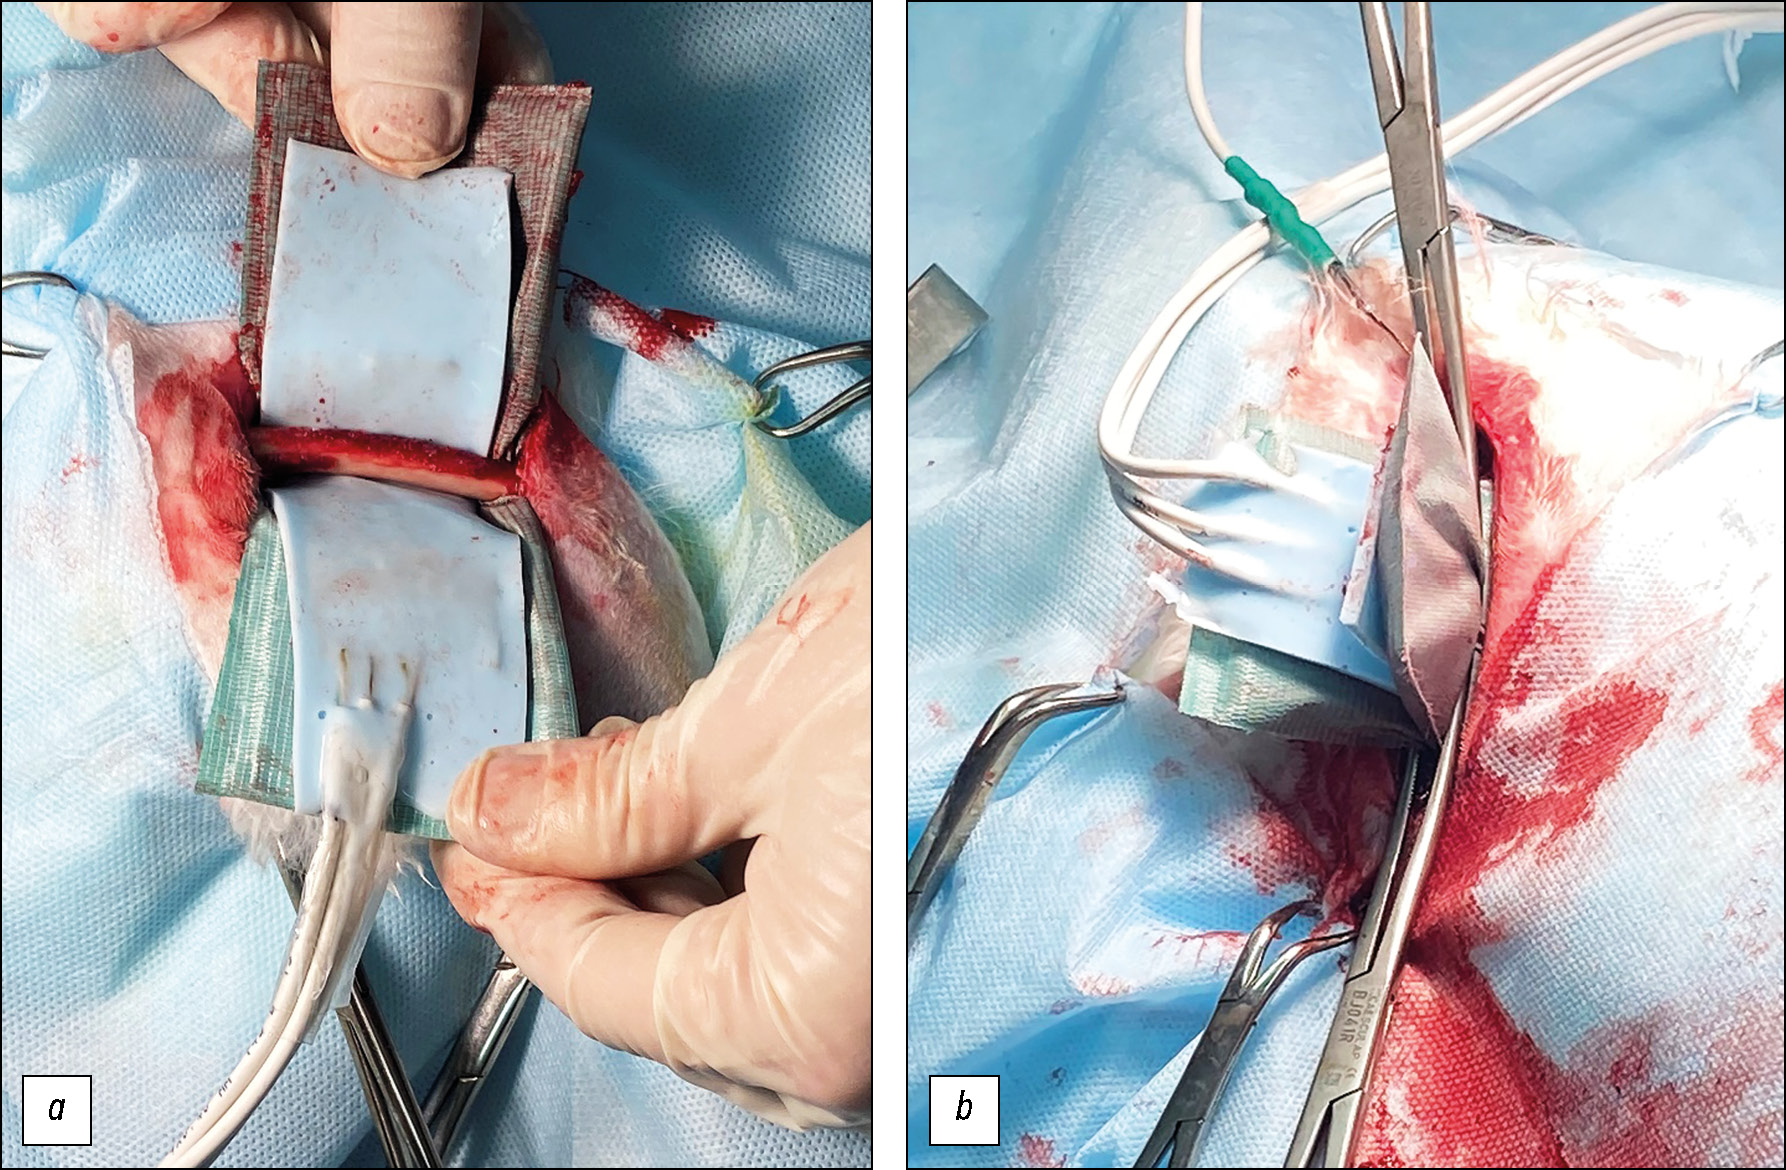

Операцию проводили в соответствии с правилами асептики. После трёхкратной обработки операционного поля раствором антисептика (Мираксидерм Трис, МИРАЛЕК, Россия) выполняли продольный разрез кожи длиной до 8 см. Острым путём осуществляли доступ к бедренной кости через волокна двуглавой мышцы бедра с последующим выполнением гемостаза. Бедренную кость скелетировали распатором. Вне зоны термоабляции выполняли трепанацию сверлом (диаметр 2 мм) для интрамедуллярного введения термодатчика Pt 100 (ПромЭл, Россия) для контроля температуры в костномозговой полости. На скелетированный участок кости циркулярно накладывали поверхностный гибкий нагреватель и термоизоляционный материал, разграничивающий область термоабляционного воздействия и окружающие ткани (рис. 1).

Рис. 1. Термоабляционное воздействие: a — накладывание нагревателя и термоизолирующей прокладки; b — нагревание кости

Fig. 1. Thermoablation: a — application of a heater and thermal insulating pad; b — bone heating

Далее осуществляли наружное термоабляционное воздействие (рис. 1) в соответствии с параметрами, приведёнными в табл. 1. Поскольку при нагревании средняя температура в костномозговом канале статистически значимо не различалась между экспериментальными группами, было возможно провести сравнительное исследование в динамике, то есть спустя 3 и 7 суток после оперативного вмешательства (табл. 1).